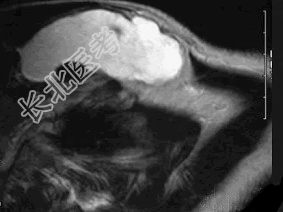

- 多项选择题37岁女性,左侧颈部肿块渐进性增大, 无压痛,局部皮温不高, CT、MRI扫描如图所示,请选择正确的描述或诊断 ( )

A、CT发现左侧颈后三角区可见低密度肿块影

B、增强扫描未见强化

C、MRI的T

WI呈低信号D、MRI的T

WI呈高信号,其内可见分隔E、考虑为淋巴管囊肿